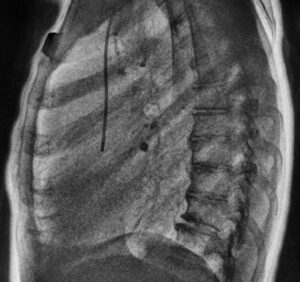

KA Imaging’s patented SpectralDR technology allows for clear differentiation between bone and soft tissue without motion artifacts, all within a single X-ray exposure. For example, in a chest X-ray, technicians can access an image of the lungs with the ribs subtracted. This greatly assists in diagnosis, removing obstructions (like bones) that can hide important medical information. Below is an example of three images produced with a single exposure using Reveal 35C. The example highlights a lateral view, not available with older dual-energy technologies:

dual energy CXR spectral dr vs. bone suppression technology